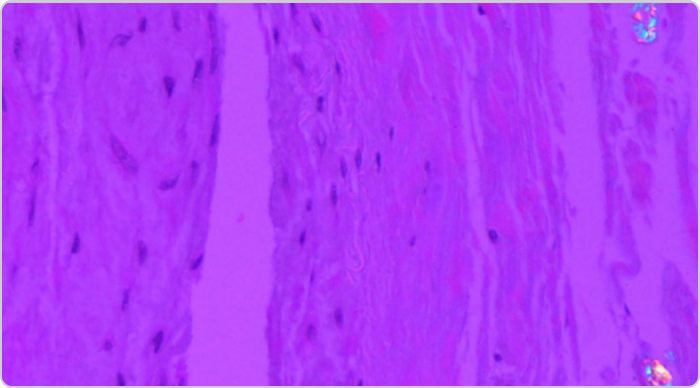

High power view of a tophus

High-power view of a tophus, with central urate deposition surrounded by mononuclear inflammatory cells and scattered giant cells.1

Adapted from Nickeleit V, et al. Nephrol Dial Transplant. 1997;12:1832-1838.

KRYSTEXXA has not been studied to reverse damage to the kidneys or any of the body's organs.